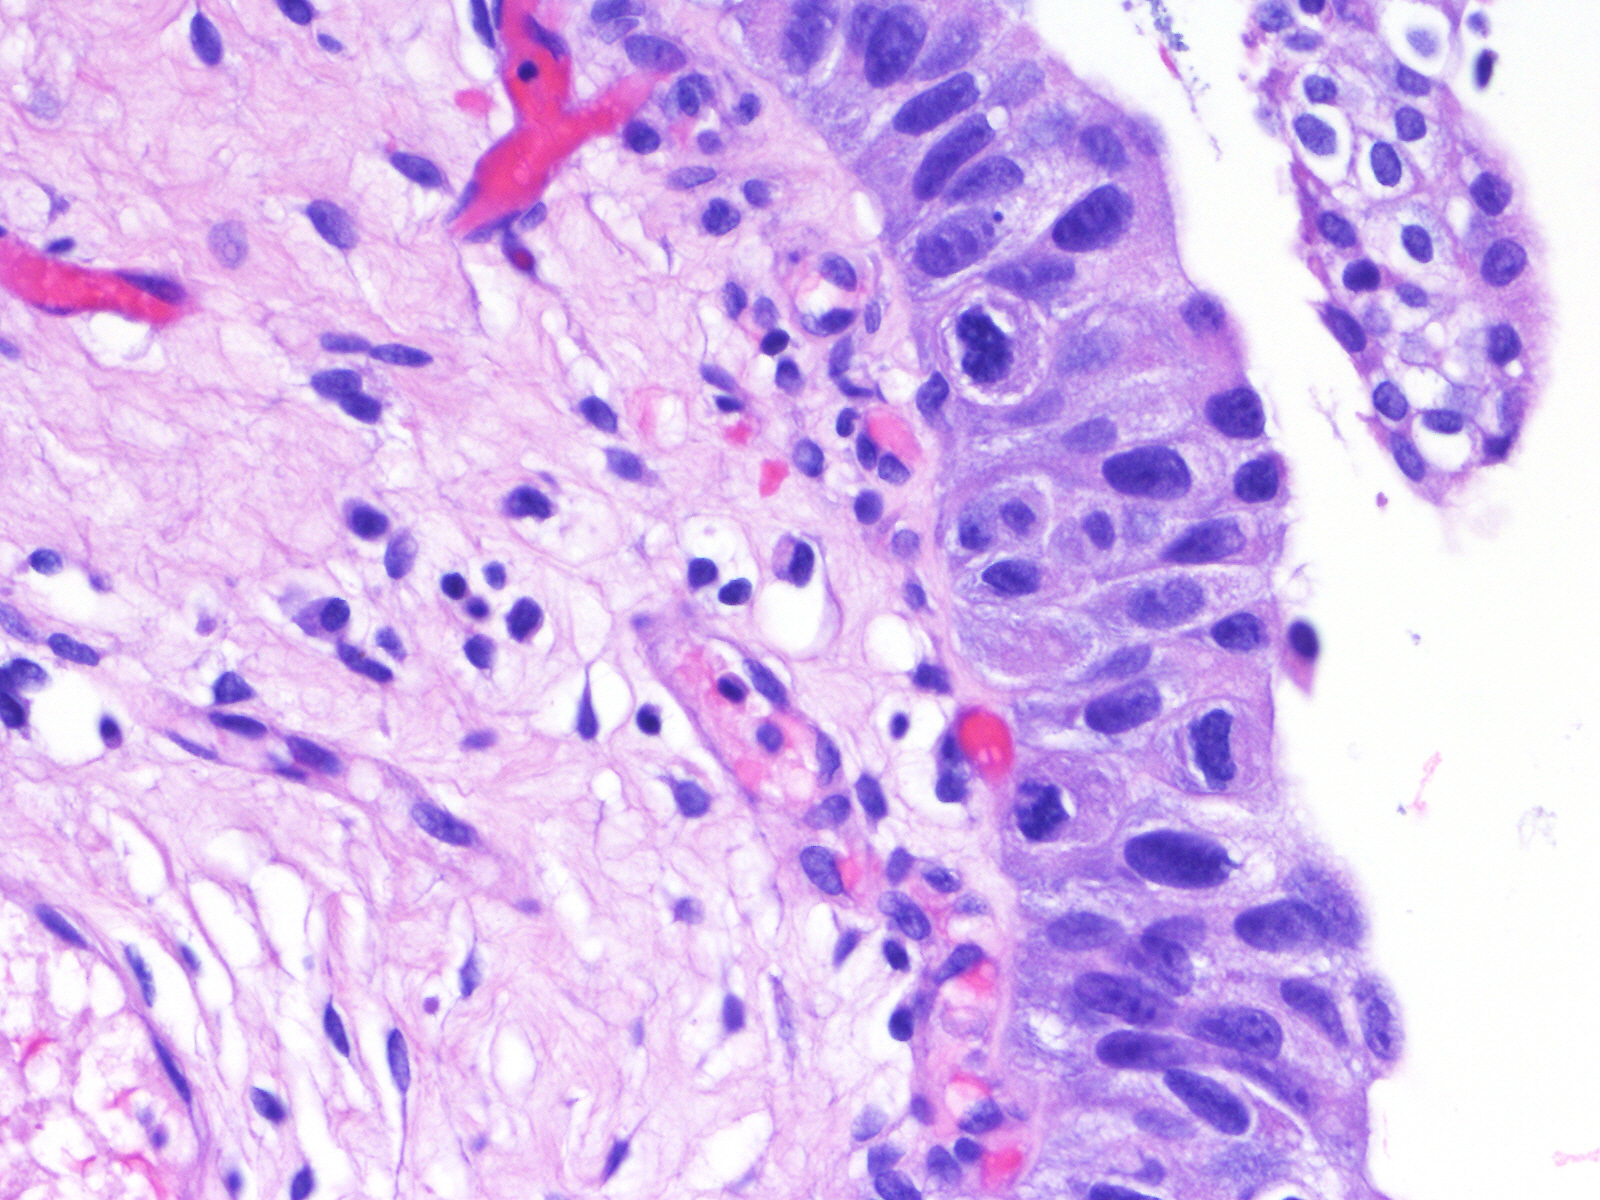

Consensus grade: Carcinoma in situ (CIS)

A 60-year-old man had atypical urothelial cells on urine cytology. Cystoscopy revealed several lesions in the bladder that were biopsied. He had a history of bladder urothelial CIS treated with intravesical BCG therapy and 3-month follow-up cystoscopies and cytologies were unremarkable.